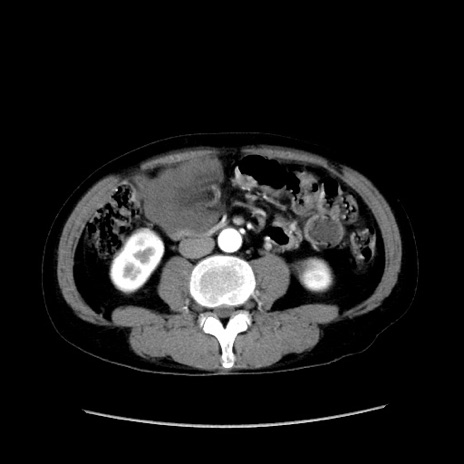

症例37(横断像)

【症例】40歳代 男性

【主訴】腹痛

【現病歴】4時間ほど前に電車に乗車中に臍部上より腹痛出現。徐々に増悪し起立困難となり、救急外来受診。生ものは数日食べていない。今朝お雑煮を食べた。

【身体所見】BT 36.8℃、BP 117/84mmHg、HR 91/min、SpO2 97%、苦悶様、腹部:臍上部広範囲圧痛あり、反跳痛±

【データ】WBC 8100、CRP 0.03